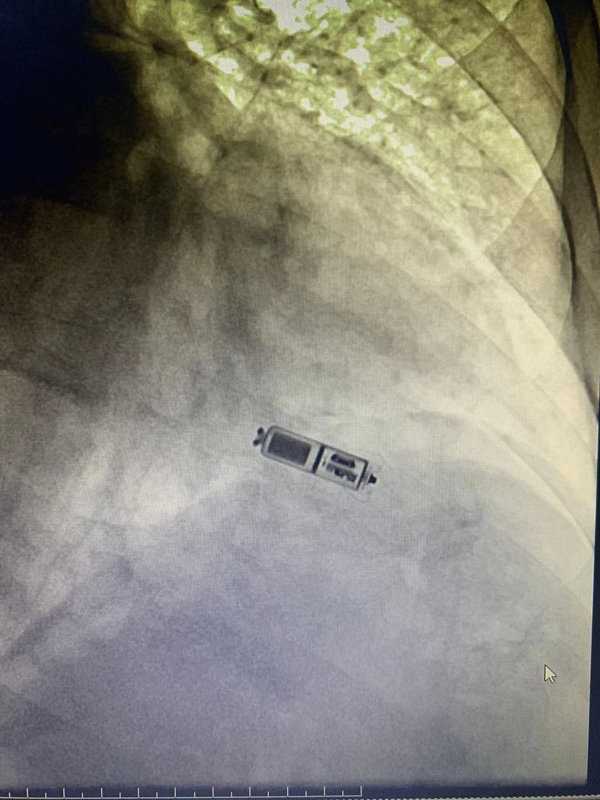

手术当天,在进行局部麻醉后立即展开手术,“战士们”以闫爷爷腿上的股静脉作为通路,通过递送系统使起搏器在闫爷爷右心室最佳位置精准“着陆”,小小起搏器好似小“风筝”放飞开来,开始启动各项工作。整个手术仅耗时30分钟。

无导线起搏器重量1.75g,体积和重量为传统起搏器的十分之一,外观看起来犹如一枚普通胶囊。

“我院使用全新投用的无导线起搏器,开启了医院心脏起搏新的‘技术革命’,为患者带来了福音。”刘思泰介绍,无导线心脏起搏器将起搏导线和脉冲发生器两者合二为一,它只需通过股静脉穿刺直达心脏,无需像传统起搏器植入术那样开刀,大大降低感染的风险。